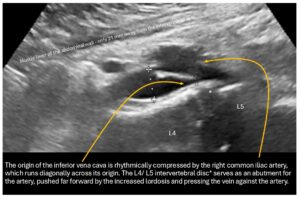

The outflow from the right pelvic hemisphere is also impaired because, as a result of the steep sacrum and significant forward tilt of the pelvis as an expression of increased lumbar lordosis, the origin of the vena cava is also pushed and compressed from the dorsal side, so that the sagittal vessel width is only 3 mm.

This leads to a significant acceleration of flow at the transition from the right common iliac vein to the vena cava from 29 to 76 cm/s.

This creates an obstruction to drainage for both hemispheres of the pelvis, which particularly exacerbates the patient’s symptoms, as despite the absence of symptoms of pelvic congestion, the pelvic veins fail as collateral circulation of the congested left renal vein (described below).

The increased lumbar lordosis manifests itself in the fact that the minimum distance between the front edge of the spine at the level of the L3/L4 intervertebral disc and the inner abdominal wall is only 20 mm. This is highly likely to lead to conflicts between the filling small intestine and the vessels in the vicinity, especially the veins, as the filling small intestine reaches a thickness of 20-25 mm. Therefore, a postprandial increase in compression of the vena cava and, if necessary, also of the pelvic veins is to be expected.

In addition, the right common iliac vein is rhythmically pushed against the promontory by the slightly elongated right common iliac artery, causing intermittent, almost complete collapse of the right pelvic vein at the pelvic outlet.